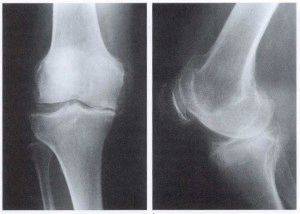

Коленный гонартроз довольно легко поддается лечению в начале заболевания, при 3 или 4 стадии деформирующего гонартроза ситуация обстоит намного сложнее. Полностью восстановить сустав затруднительно, присутствуют степени деформации.

При составлении схемы, согласно которой проводится лечение гонартроза третьей степени, в первую очередь принимаются необходимые меры для снятия болевого синдрома. Затем медики занимаются купированием воспалительного процесса и восстановления подвижности. Если принятые медикаментозные меры не дают результата, при третьей степени, при четвертой, потребуется проведение операционного вмешательства.